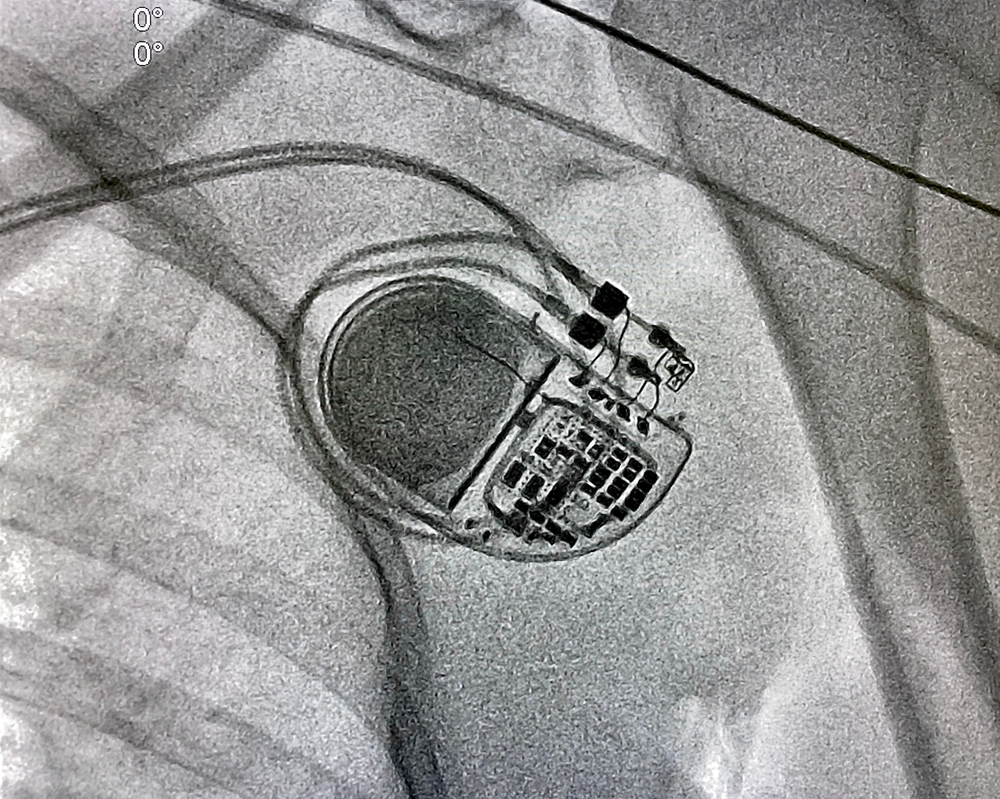

The implantation of a pacemaker device requires surgical intervention. 1 to 3 small electrical lines are implanted in the heart’s chambers, and the generator contains the battery and circuitry needed to keep the heart beating at the proper rate. A pacemaker is a medical device that uses electrical pulses to stimulate heartbeats while maintaining a regular rhythm.